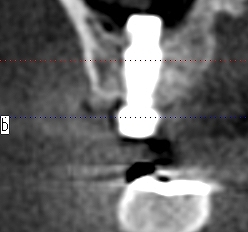

していきました

このように埋入しています